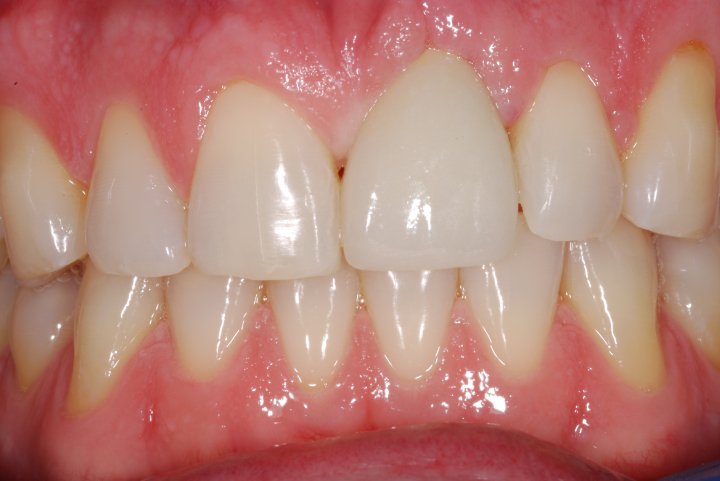

Final

One Year Post Op Healing Picture

Procera Full Porcelain Crown In The Implant